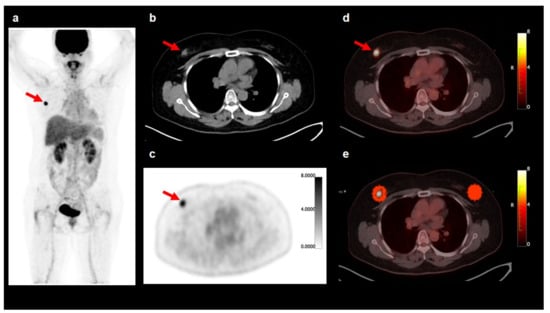

2.3. FDG PET/CT Image Analysis

3.2. Comparison of Breast AT Imaging Features